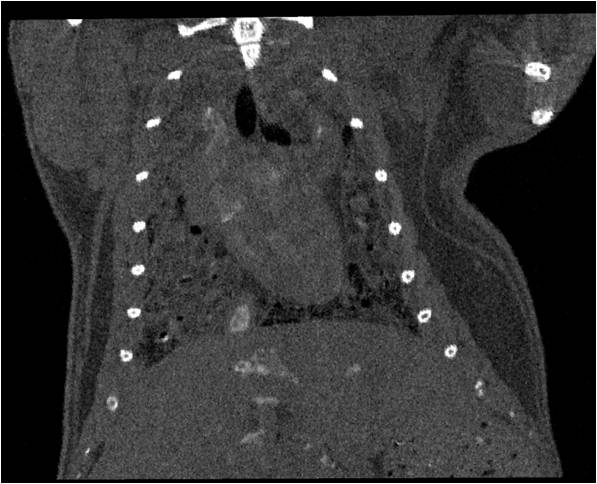

肺轉(zhuǎn)移

小鼠模式,22.5μm像素

正常

正常.jpg

8天 14天

8天.jpg 14天.jpg

無造影劑注入 造影劑注入